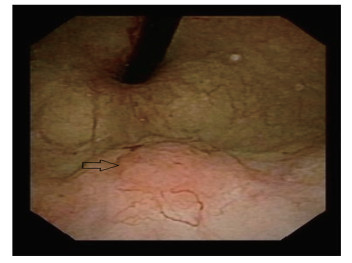

本次入院膀胱镜检查发现膀胱左侧壁1枚乳头样肿物,见图 1。CTU检查显示:膀胱左侧壁局限性增厚,平扫CT值约50 HU,增强扫描可见强化结节,直径约1.5 cm,基底较宽,CT值约74 HU,延迟期局部略充盈缺损,见图 2。泌尿系统彩色多普勒超声显示:膀胱左侧壁1处隆起样回声,大小约1.73 cm×1.27 cm,形态不规则,膀胱壁欠光滑。头部及肺部CT、肝胆脾超声、尿常规等检查均未见明显异常。术前诊断:膀胱恶性肿瘤。全身麻醉下行膀胱部分切除术。术后病理诊断:LELC (侵及肌层)。免疫组织化学结果:CK20 (-),CD30 (-),P63 (+),GATA-3(+),CD45 (LCA) (+),CD15 (散在+),P53 (散在+),CK (部分+),CK7 (部分+),Ki-67 (约50%+),CD3 (T细胞+),CD20 (B细胞+),HE染色切片见图 3。结合术前检查结果和术后病理结果最终诊断为膀胱淋巴上皮瘤样癌(lymphoepithelioma-like carcinoma of the bladder,LELCB),临床病理分期:pT2N0M0。术后1个月开始行多西他赛联合顺铂(DP方案) 辅助化疗。术后随访15个月,患者一般状态良好,无肿瘤复发和转移迹象。本研究已获得患者知情同意。

| 图 1 术前膀胱镜检查见膀胱左侧壁1个乳头样肿物 |